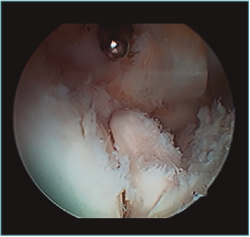

Acto seguido, realizamos nuestra secuencia de trabajo descrita anteriormente (visualización, creación de espacio, trabajo óseo y trabajo de partes blandas). El fresado óseo debe realizarse siempre con el instrumental motorizado orientado hacia el húmero, para evitar las lesiones de partes blandas. El uso de fresas o el sinoviotomo en modo no oscilante y a alta velocidad nos permitirá eliminar los osteofitos que interfieran con la movilidad, especialmente aquellos que ocupan la fosa radial o coronoidea (Figura 8). También es frecuente tener que eliminar osteofitos que aumentan la altura de la coronoides (Figura 9). Una vez eliminado el material óseo (Figura 10), flexionamos el codo para comprobar el aumento de flexión conseguido, que no será completo hasta que liberemos la cápsula posterior y la banda posterior del ligamento colateral medial. Como último paso en la cámara anterior, procedemos a la eliminación de la cápsula articular. Introducimos un Basket recto desde el portal anteromedial y vamos mordiendo la cápsula, atrapándola, cortándola y realizando un movimiento de batido hacia proximal para separar el fragmento capsular de las partes blandas anteriores. Progresamos lateralmente, descubriendo el vientre muscular del braquial anterior, hasta que aparezca tejido graso detrás de la cápsula resecada. En este momento, cambiamos los portales y miramos desde el portal anteromedial proximal y utilizamos la pinza Basket desde el portal anterolateral. Una vez realizada esta capsulotomía amplia, usamos el sinoviotomo para eliminar los restos capsulares proximales. Durante todo este proceso, utilizamos un retractor desde el portal anterolateral proximal para tensar la cápsula y proteger, sobre todo, el nervio radial, que queda situado justo en la grasa lateral al músculo braquial y anterior a la cabeza del radio, y a escasos milímetros de nuestro instrumental de trabajo; aunque no es aconsejable, es posible traccionar de él e introducirlo en la articulación con ayuda de un palpador introducido en la grasa que lo recubre. El nervio mediano se encuentra medial al músculo braquial, pero en un plano bastante más anterior, lo cual hace que esté mucho más protegido(12,13).

Figura 8. Osteofitos ocupando la fosa radial y coronoidea, observados desde el portal anteromedial proximal.

Figura 9. Osteofito coronoideo observado desde el portal anterolateral.

Figura 10. Mismo caso que en las Figuras 8 y 9 después del trabajo óseo. Obsérvese la recreación y fusión de ambas fosas radial y coronoidea con el típico aspecto de “tobogán” después del fresado de la cara anterior del húmero y la disminución de la altura de la coronoides. Todavía no se ha procedido a realizar la capsulectomía.